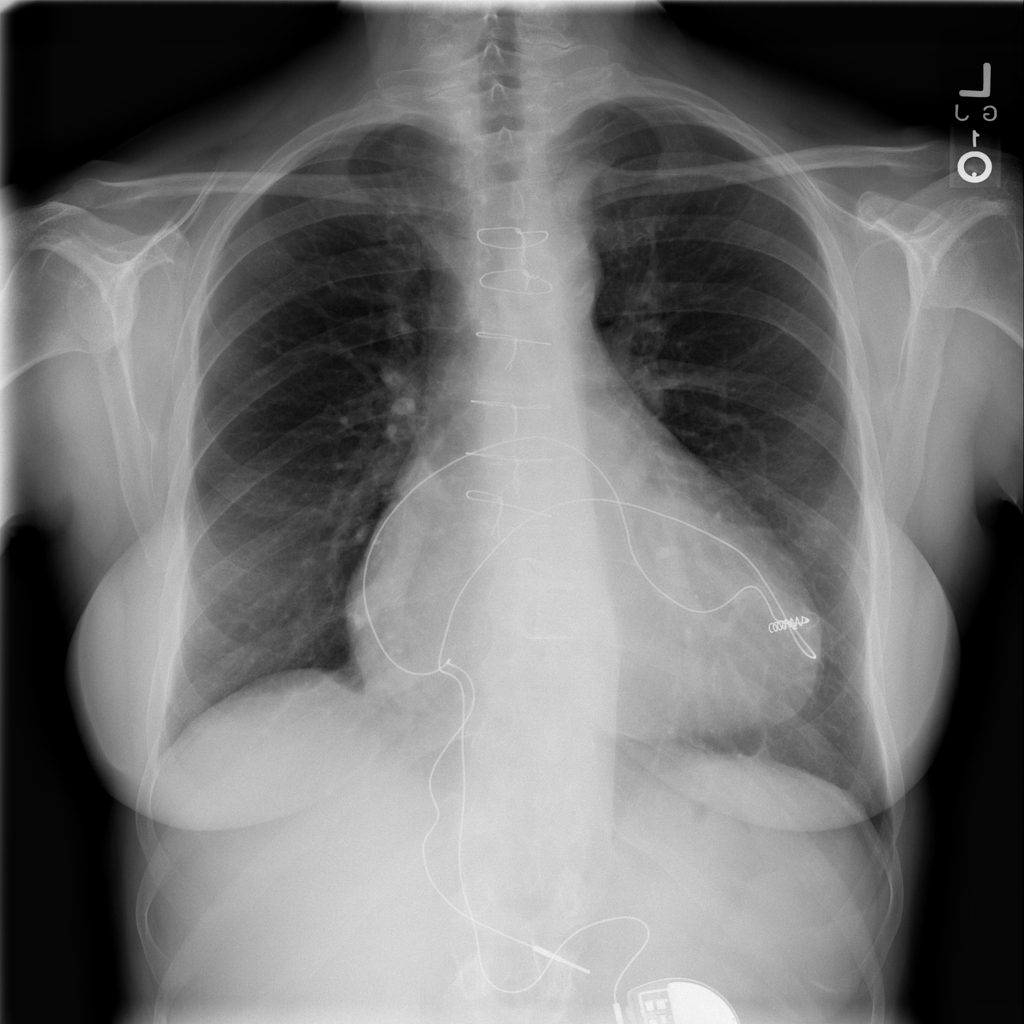

PAT-F3E7 · IMG-000Cardiomegaly

PAT-F3E7 · IMG-000

PA